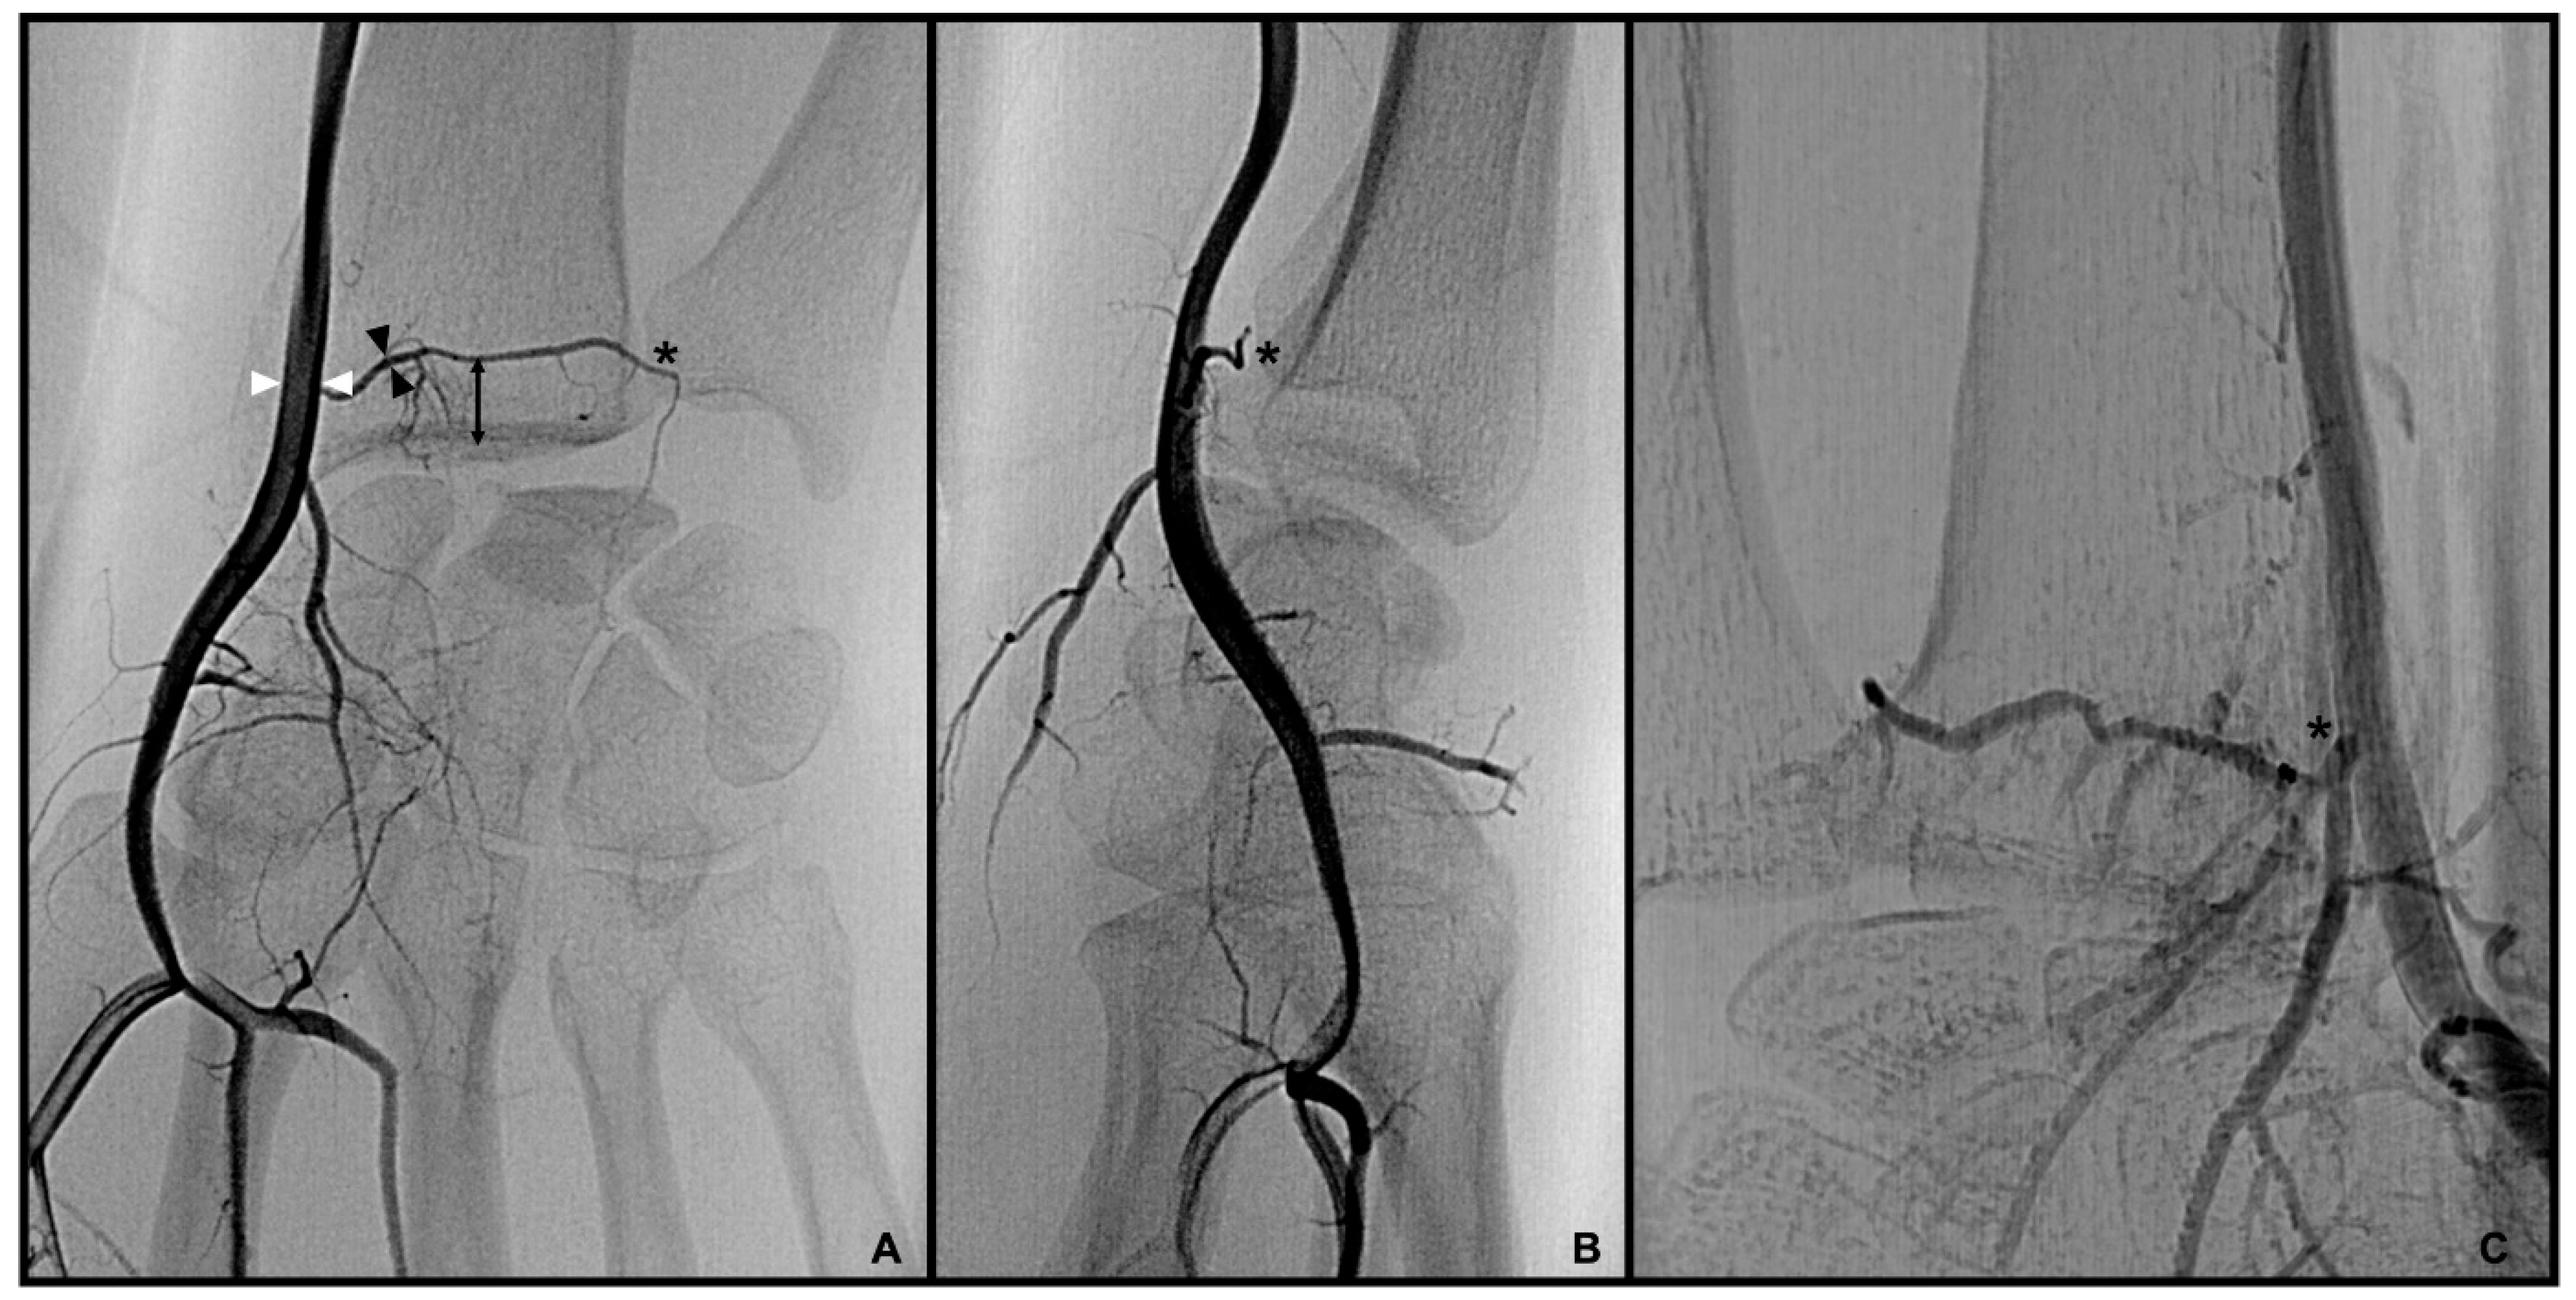

3.1. Palmar Radiocarpal Artery and Palmar Radiocarpal Arch (PRCA)

3.2. Dorsal Carpal Branch of the Ulnar Artery (DCBUA)

3.3. Anterior Interosseous Artery (AIA)